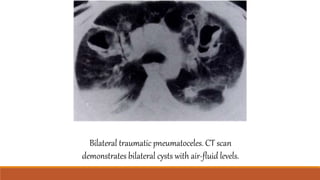

Three predominatepatterns are observed

Ground-glass change with geographic distribution

Ground glass opacities with interlobular septal thickening

Nodular opacities: no zone predominance or gravity dependence in the nodular pattern

CT at left shows

multiplenodular

densities and patchy

airspace disease

scatteredthroughout

both lungs

FAT Embolism Three predominatepatternsare observed Ground-glass change with geographic distribution Ground glass opacities with interlobular septal thickening Nodular opacities: no zone predominance or gravity dependence in the nodular pattern

CT at leftshows multiplenodular densities and patchy airspace disease scatteredthroughout both lungs